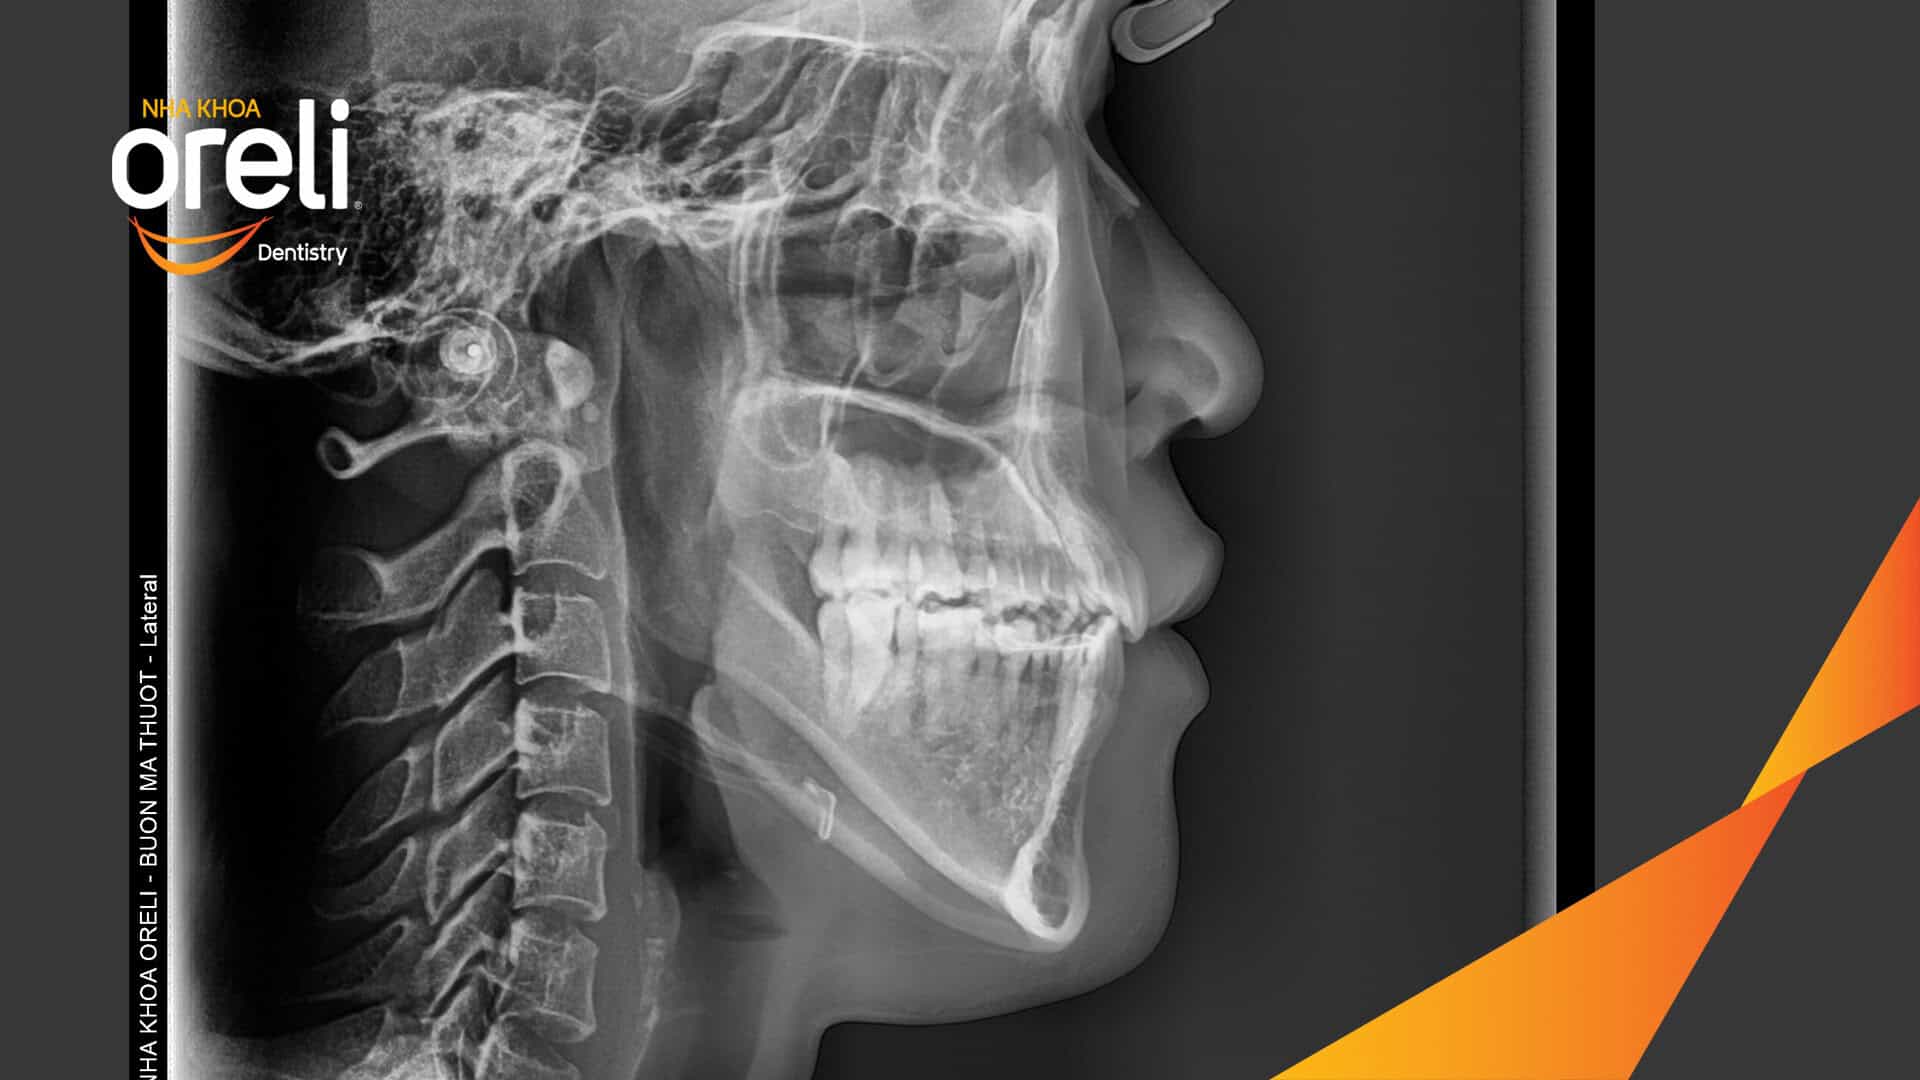

Hành trình thay đổi nụ cười ca lệch khớp cắn hạng 3, hàm dưới trượt ra trước và nhô xương hai hàm.

Tình trạng này không chỉ ảnh hưởng đến thẩm mỹ khuôn mặt mà còn gây khó khăn trong ăn nhai và phát âm. Thông qua quá trình niềng răng được cá nhân hóa, khách hàng đã từng bước cải thiện khớp cắn và lấy lại sự tự tin trong giao tiếp.